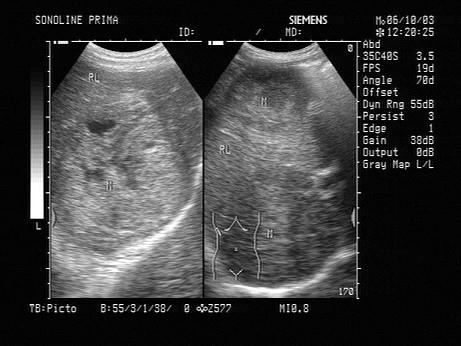

问题 男,57岁,慢性乙肝多年,现上腹痛,纳差,AFP>500,结合超声声像图,诊断为?(?)

选项 A.肝血管瘤 B.肝脓肿 C.结节性肝硬化 D.弥漫性肝癌 E.脂肪肝

答案 D